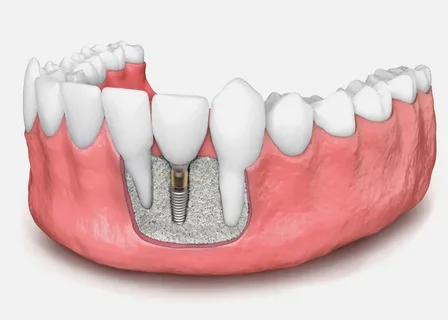

Your gateway to a perfect smile with Dr. Asmaa Askar. Offering professional implants, veneers, and pediatric dentistry using advanced Swiss & German technology in Fifth Settlement & Al Rehab. Trusted care for the whole family.

If you are looking for the best dentist in New Cairo and Al Rehab, Triple A Dental Clinic, led by Dr. Asmaa Askar, offers the perfect blend of global expertise and 2026 digital technology. We are committed to compassionate care and superior precision, ensuring a painless treatment experience. Our integrated specialties include: Dental Implants (using top Swiss & German systems), Invisalign (Clear Aligners), Laser Teeth Whitening, and Hollywood Smile, along with excellence in Root Canal Treatment, Zirconia Crowns, Cosmetic Fillings, and Gum Care—plus a specialized department for Pediatric Dentistry. With a 5.0-star rating and proven results, we guarantee comfort and excellence in the heart of New Cairo. Book your appointment now and design the smile of your future